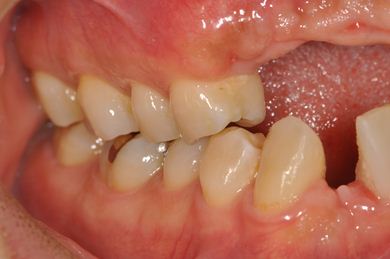

| 性別/年齢 | 男性 / 36歳 | ||||||||||||||||||||||||||||||||

| 主訴 | 事故で欠損した上部の歯4本、下1本のインプラント治療相談。 | ||||||||||||||||||||||||||||||||

| 治療内容 | インプラント2本(GBR、自家骨移植)、メタルボンドセラミック4本、結合組織移植術 | ||||||||||||||||||||||||||||||||